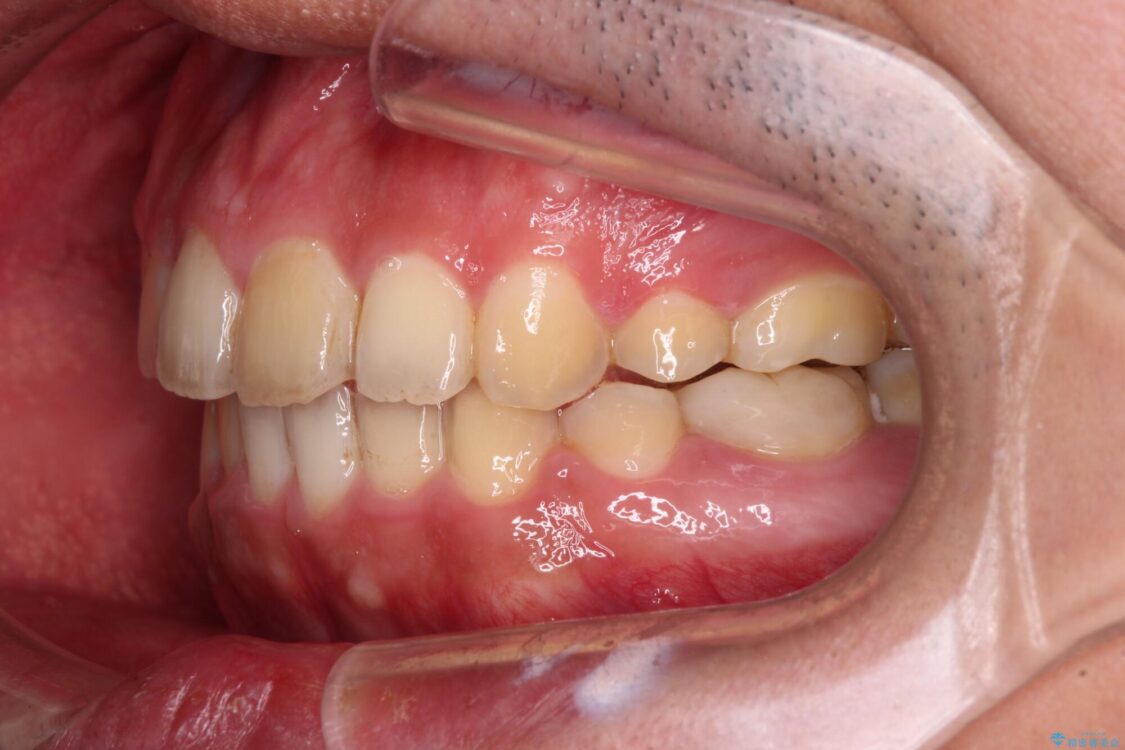

治療後について

下顎骨が左側に変位しているため、正中が合わないことは予想できましたが、歯列が整った後も咬み合わせが安定せず、咬み合わせを落ち着かせるために1年以上の期間を要しました。

噛みにくさの改善に時間がかかってしまうことがインビザラインの欠点の1つといえます。

治療後

• 後戻りでデコボコの前歯 インビザライン矯正治療 治療後画像